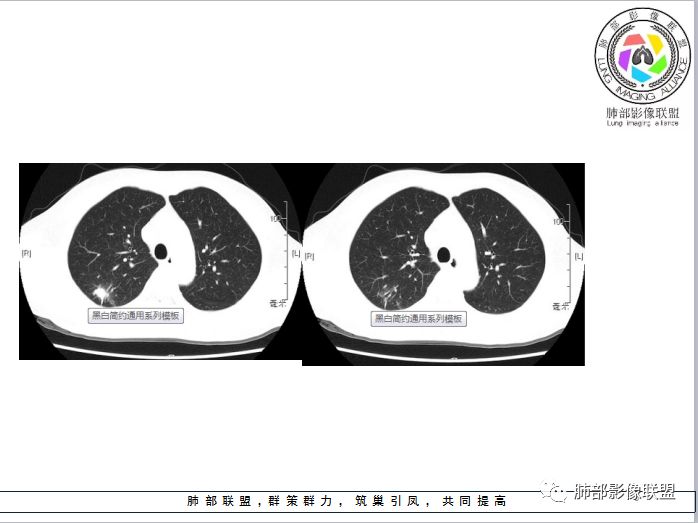

中年男性,右肺上叶胸膜下薄壁空洞,内壁光滑,周围长毛刺及索条,边缘模糊,邻近胸膜轻度牵拉,周围卫星灶。增强轻中度强化。考虑炎性,结核>隐球

空洞结节,内壁光滑,边缘纤细长毛刺,无强化,周围卫星病灶,考虑结核。

右肺上叶结节伴空洞形成,轻度强化,周围胸膜牵拉,可见卫星灶,没看见近端支气管的情况。考虑结核可能性大,矢状位见壁结节,SUV2.9,也要警惕肺癌可能。建议穿刺。

中年男性,右肺上叶后段结节伴空洞,空洞壁光滑,厚薄不一,边缘见多发细长软毛刺,强化为轻度强化,PET显示病灶代谢不高,考虑为良性病变,结核可能

胸膜下肿块,洞壁光整,边缘细长毛刺及索条,未见明显强化,考虑结核,曲霉,鉴别腺癌。

右肺上叶后段近胸膜下空洞结节,长轴平行于胸膜,边缘部分膨隆,部分平直,长短毛刺,胸膜凹陷征,边缘磨玻璃影清晰,内壁光整,矢状位见壁结节,壁轻度强化。中年男性,粉尘接触史,腺癌>结核

右肺上叶空洞性结节,形态欠规则,边缘毛糙可见毛刺,空洞壁厚薄欠均匀,壁内可见小结节,近端支气管截断,远端牵拉胸膜,病灶收缩,增强后可见空洞壁强化不明显,PET的SUV未见明显摄取,考虑炎性肉芽肿(隐球,结核)鉴别腺癌

中年男性,52岁,无症状。胸部CT:右上肺后段胸膜下结节,内见空洞,洞壁光滑,内有壁结节,病灶边缘细长毛刺,病灶周围胸膜牵拉凹陷,强化不明显。考虑:<3cm,无GGO,无淋巴结,强化不明显,粉尘接触史加部位,首选炎性结节,结核空洞?鉴别Ca。胸膜牵拉程度与病灶性质关系,静待老师们进一步分析。

右肺上叶尖段小结节,内部偏心空洞,近肺门侧,洞壁光滑,边缘不整,多发细软毛刺,胸膜缘可见轻度牵拉,近胸膜缘长索条,有芋艿须的感觉,邻近病灶肺野可见淡薄絮状密度增高影,边缘不清,周围肺野内可见小卫星灶,增强后无明显强化,纵隔内无明显肿大淋巴结,结合临床,老年男性,无明显临床症状,综合考虑感染性病变,结核首选,鉴别隐球;